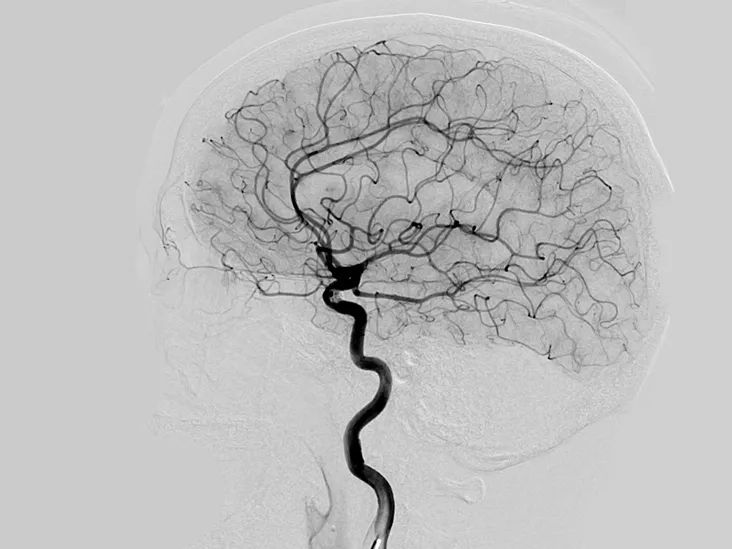

△ 血管造影术(angiogram)拍到的脑部血管。 血管造影术是利用X光观察血管堵塞的医学方法。